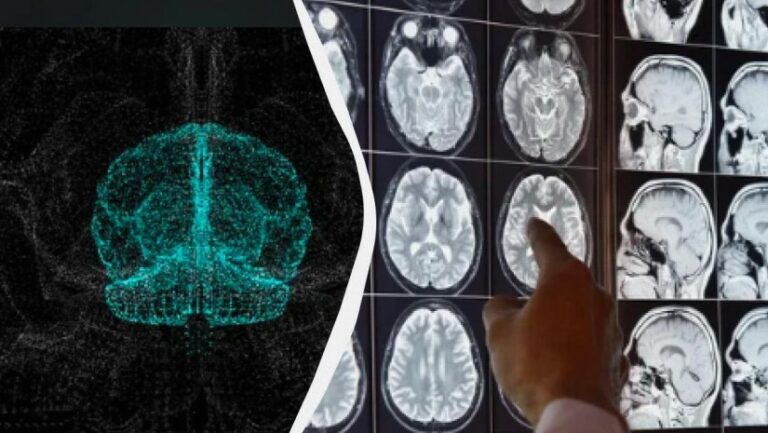

ალცჰაიმერის მკურნალობაში გარღვევაა – მეცნიერების მოულოდნელი აღმოჩენა

მეცნიერებმა აღმოაჩინეს, რომ ნაწლავის ბაქტერიების ერთ ტიპს აქვს სხვადასხვა ტიპის ცილებთან რეაქციის უნარი. ეს დემენციის ყველაზე გავრცელებული მიზეზის – ალცჰაიმერის დაავადების მკურნალობის…